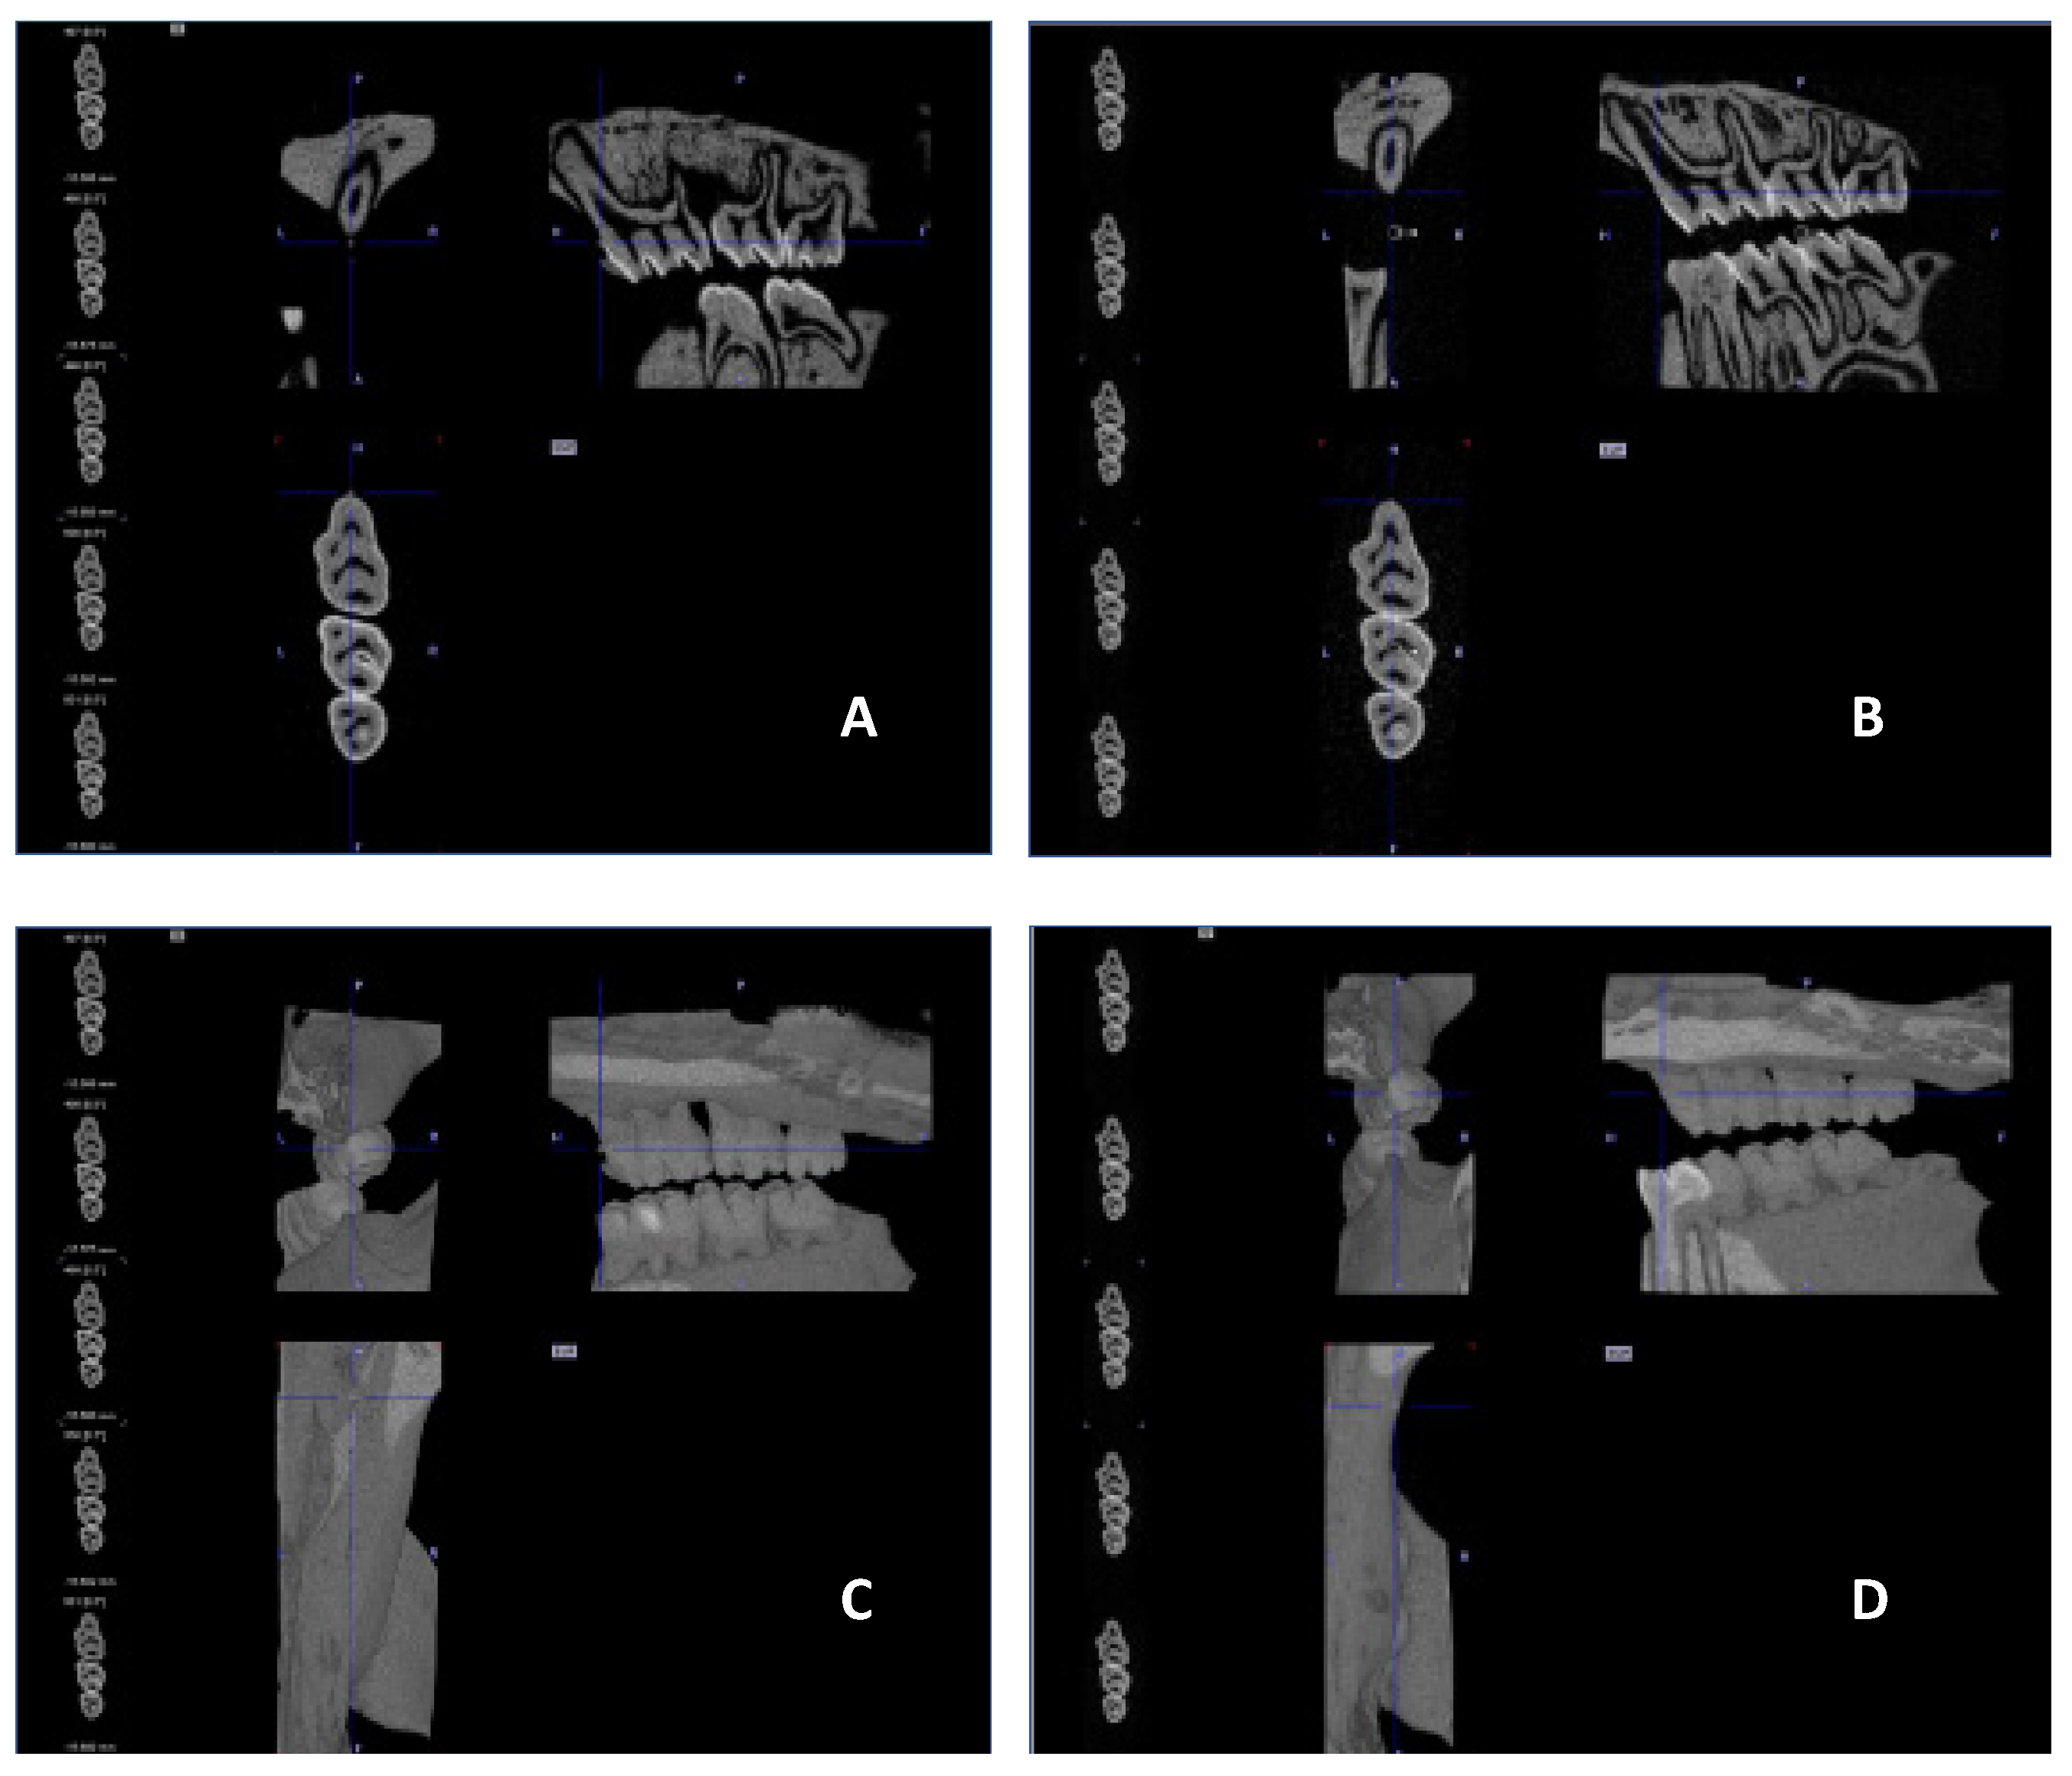

No visible changes were noted in the periodontium. Furthermore, CT scans revealed no alterations in the jawbone area. Due to technical constraints, the experiment was confined to the upper jaw, and alveolar bone loss was quantified using micro-computed tomography (μCT). Measurements were taken from the cemento–enamel junction (CEJ) to the alveolar bone crest (ABC). For each analyzed rat (23 in total), 12 measurements were conducted: three times per molar at two sites (left and right), doubled for statistical replication. The specific distances utilized for statistical analysis are detailed in Figure 8.

Figure 9 presents a representative CT analysis of bone loss in P. gingivalis-infected animals (both minocycline-treated and controls. The beneficial effect of the treatment is clearly visible with regard to bone loss. Comparison of the CEJ-ABC distance shows a significant bone loss in the non-treated animal (A + C, PG), which was remarkably diminished by the treatment (B + D, PG+MIN-T).

This observation has been statistically validated, as shown in Figure 10. Aggregated measurements across all evaluated molars (1st, 2nd, and 3rd upper molars) indicate a significant reduction in bone loss in the treated group PG+MIN-T, with a p-value of <0.0001 compared to the non-treated group (PG). This demonstrates the antibiotic’s effectiveness over 31 days following treatment with the novel formulation.

4.6.1. Micro-Computed Tomography Analysis

To determine bone loss High Resolution Animal Computed Tomography (Micro-CT, MILabs, The Netherlands) was used. All animals were scanned at two time points (before treatment (T0) and on the day of termination of the experiment (TEND)). Imaging was performed at an ultra-focus magnification, 50 kV source voltage, and 0.21 mA current. Three-dimensional images were obtained using the PMODE software (vers. 4.3; Fällanden, Switzerland). To assess the alveolar bone loss, a linear distance from CEJ to ABC of each tooth of the lower and upper jaw was measured. Each measurement was performed three times, and the data are presented as the mean ± standard deviation (SD). The results are presented as the distance after subtracting the basal measurement (T0) from the measurement obtained at the endpoint of the procedure (TEND).